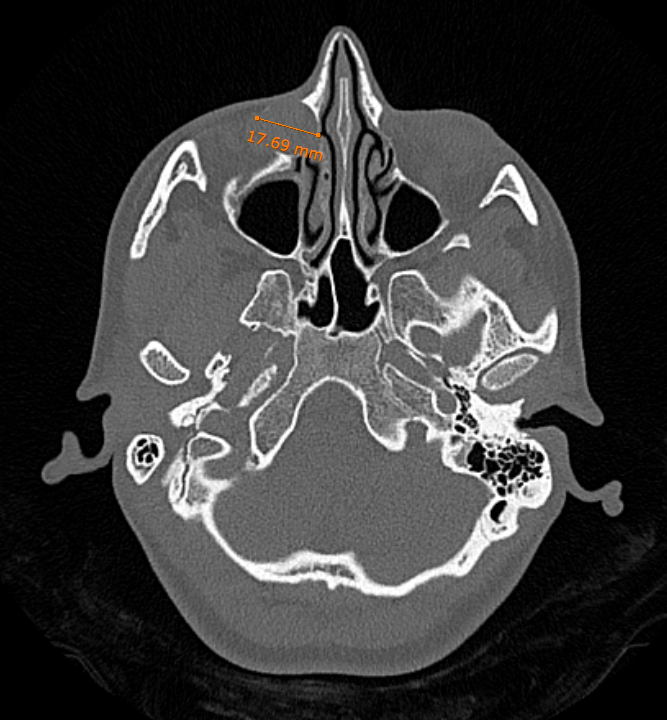

Ασθενής 38 ετών με υποτροπιάζουσες φλεγμονές του δεξιού δακρυϊκού ασκού και επίμονη δακρύρροια δεξιά υποβλήθηκε σε διάνοιξη της στένωσης ενδοσκοπικά μέσω της μύτης χωρίς εξωτερικές τομές κι ουλές και έλαβε εξιτήριο την ίδια ημέρα με πλήρη αποκατάσταση των συμπτωμάτων!